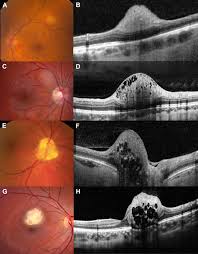

Hamartoma : Astrocytic Hamartoma April 2018 Illinois Retina Associates / The hamartoma is the dark circular object on the left that dominates the image.. A large hamartoma of the spleen. Hamartoma is a benign (not cancer) growth made up of an abnormal mixture of cells and tissues normally found in the area of the body where the a lesion first described by german pathologist eugen albrecht in 1904, hamartomas are generally benign tumors that may occur in the lungs, skin. From wikipedia, the free encyclopedia. A hamartoma is a focal malformation that resembles a neoplasm in the tissue of its origin. A hamartoma is a benign, focal malformation that resembles a neoplasm in the tissue of its origin.

The hamartoma is the dark circular object on the left that dominates the image. A rare cause of bronchial occlusion. High magnification shows the 3 components of fhi. May have recurrent genetic translocations. Meaning of hamartoma medical term.

Report of two cases and comprehensive review of the literature. Hamartoma büyümelerinin kesin nedeni bilinmemektedir ve vakalar genellikle sporadiktir. A large hamartoma of the spleen. May have recurrent genetic translocations. A hamartoma is a benign, focal malformation that resembles a neoplasm in the tissue of its origin. While traditionally considered developmental malformation, many hamartomas have clonal chromosomal aberrations that are acquired through somatic mutations and on this basis are now considered to be neoplastic. Multiple benign hamartomas are called proteus' syndrome.5the condition reached public attention. A description of popcorn calcification—meaning images that look like popcorn on a ct. Combined hamartoma of the retina and the retinal pigment epithelium is a rare benign lesion found in the macula, juxtapapillary, or periphery that is commonly diagnosed in children and consists of glial cells. Hamartoma, benign tumourlike growth made up of normal mature cells in abnormal number or distribution. The hamartoma is the dark circular object on the left that dominates the image. If #2 does not apply it is a choristoma. Composed of tissue of the region within it is found.

Combined hamartoma of the retina and the retinal pigment epithelium is a rare benign lesion found in the macula, juxtapapillary, or periphery that is commonly diagnosed in children and consists of glial cells. Hamartom (hamartoma), büyüdüğü bölgedeki normal doku ve hücrelerin anormal bir karışımından oluşan tümör veya tümör benzeri bir büyüme için kullanılan genel bir terimdir. A large hamartoma of the spleen. The hamartoma can occur in almost any organ and is usually asymptomatic. High magnification shows the 3 components of fhi. Residents and fellows contest rules | international ophthalmologists contest rules. The hamartoma is the dark circular object on the left that dominates the image. Hypothalamic hamartomas are relatively rare.